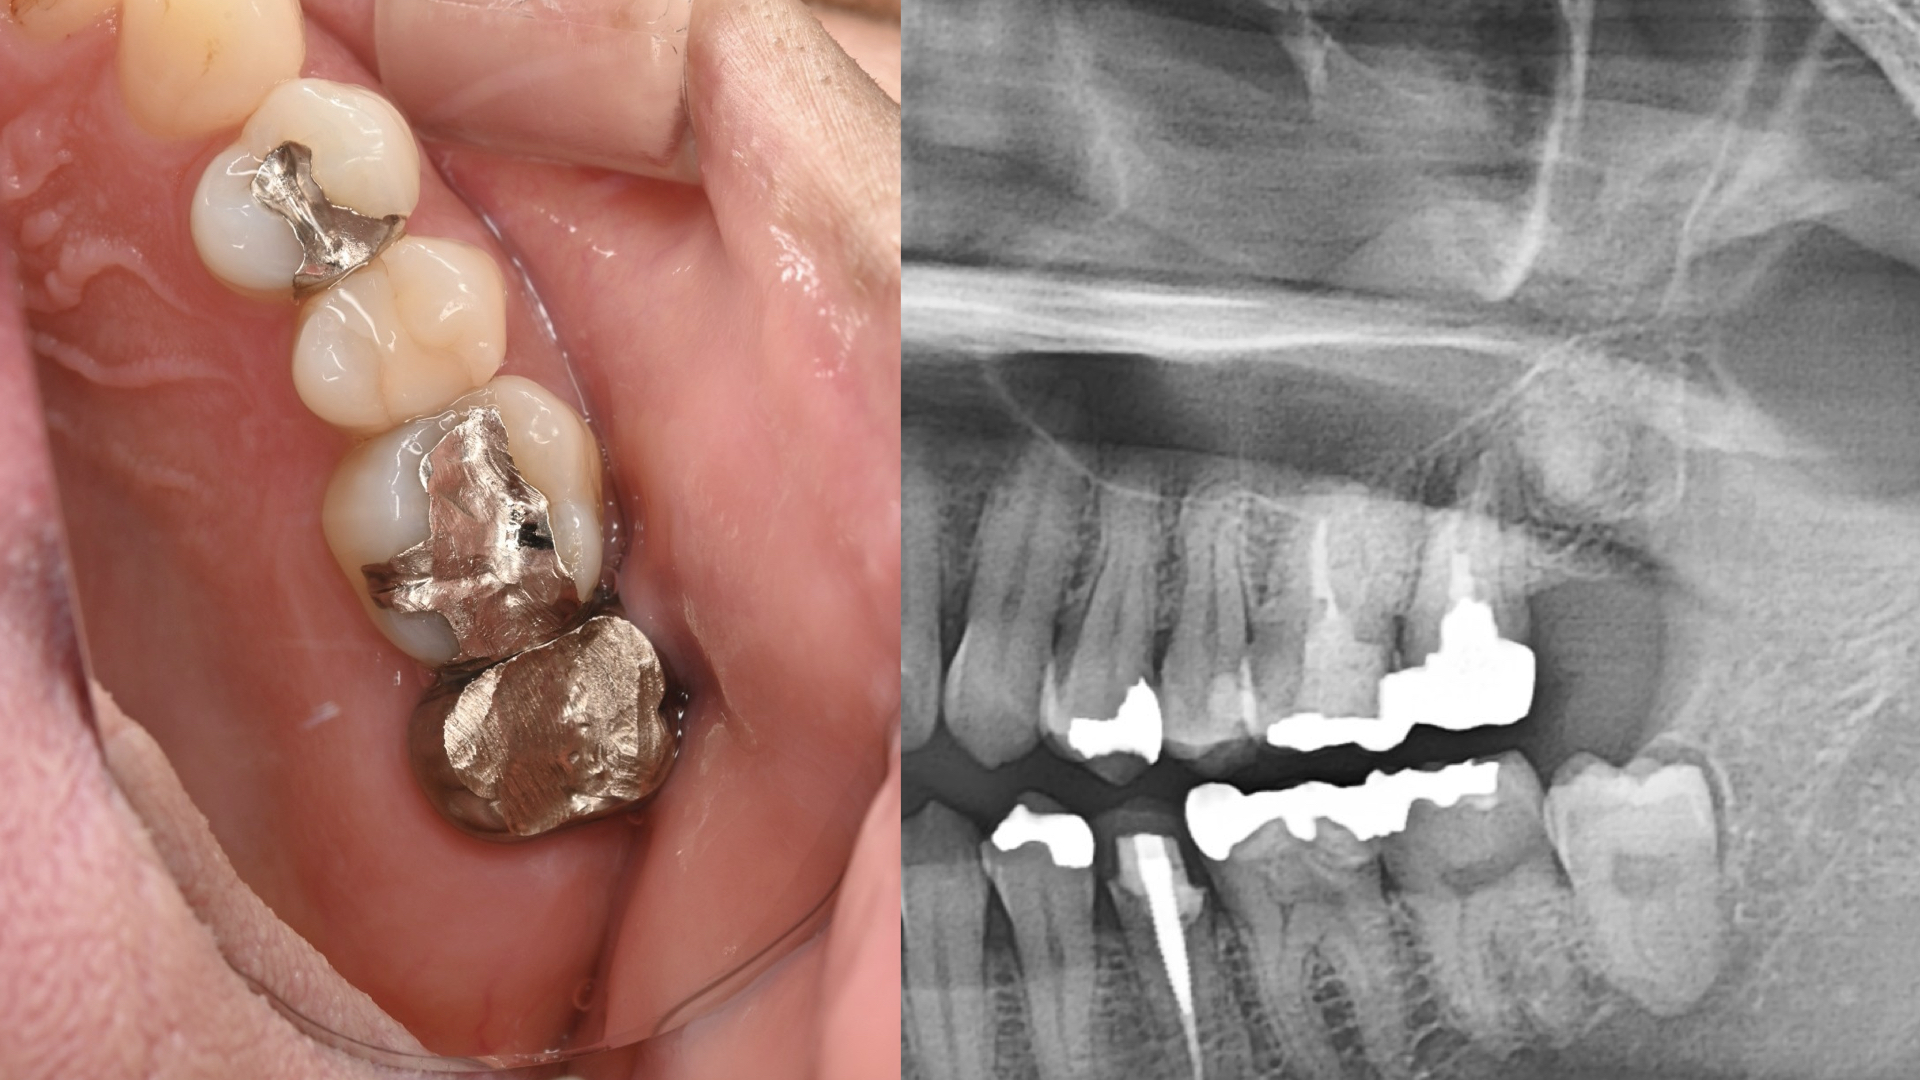

CT(3次元レントゲン)診査

- 歯の状態:歯質が骨縁上に適切な厚みを持って存在する。根尖の外部吸収様所見

- 隣在歯の状態:失活しているが、病変は認めない。

- 歯根の外部吸収を伴う根尖性歯周炎

- 上顎洞炎を伴う根尖性歯周炎

- 歯根の外側に病原の可能性があり外科的対応を治療計画に組み込む必要がある。

- 根尖部での外部吸収により根尖の拡大を認めるため細菌の押し出しに配慮した手技が求められる。

抜歯と病変部の除去

歯根切除

術直後のレントゲンと処置後の状態